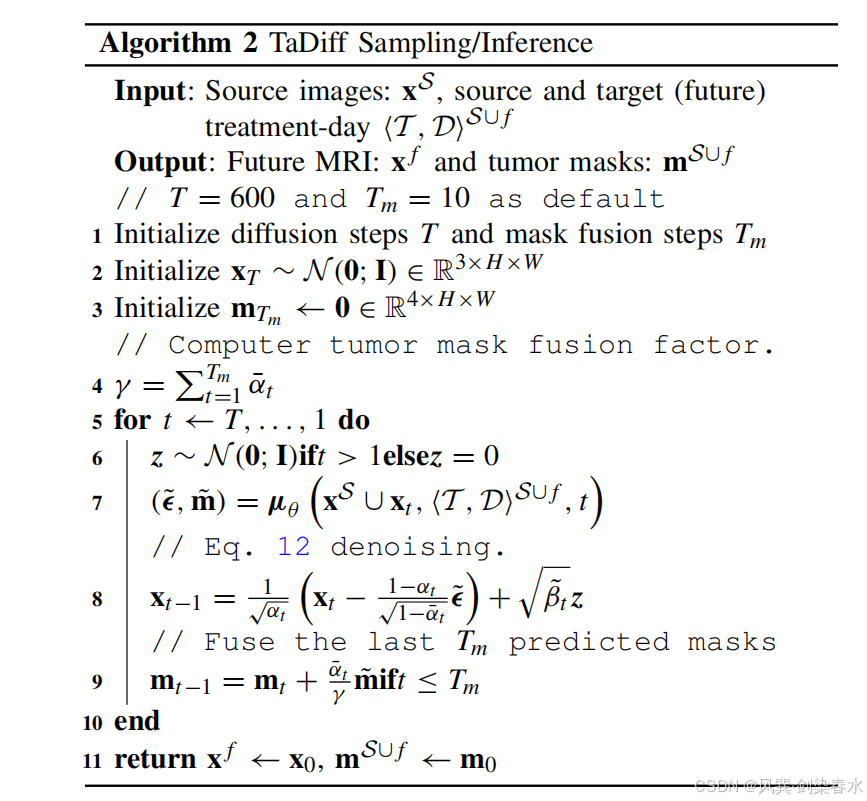

因此,TaDiff 模型不仅仅是一个纯粹的扩散模型,而是一个结合了去噪扩散和分割任务的混合网络,能够以端到端的方式生成未来的 MRI 图像并同时分割出肿瘤的纵向生长掩模。算法1 和 算法2 介绍了 DDPM 训练和采样过程。

需要注意的是,扩散分支和分割分支共享编码器组件。扩散过程需要 600 步来生成目标图像,而分割过程仅利用最后 10 步。这些最后的步骤提供了质量最高的输入,本文生成 10 个 mask。随后对这些 mask 进行加权平均,以生成最终的分割 mask。这种方法确保分割 mask 能够从扩散过程后期阶段产生的高质量输入中获益。

通过应用模型并采用多个随机采样过程(本研究中考虑了 5 次采样),可以通过计算模型在相同条件输入下的预测标准偏差,为预测的肿瘤掩模和合成的 MRI 生成像素级不确定性图。